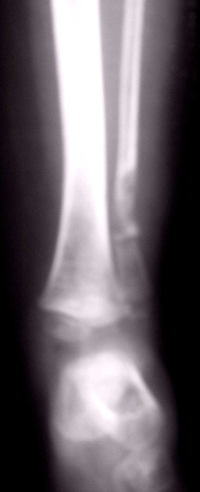

Effettuata una radiografia di controllo, al terzo distale del perone sinistro era evidente un'area litica e una pseudoartrosi in sede di pregressa biopsia (Figura�1).

Figura 1